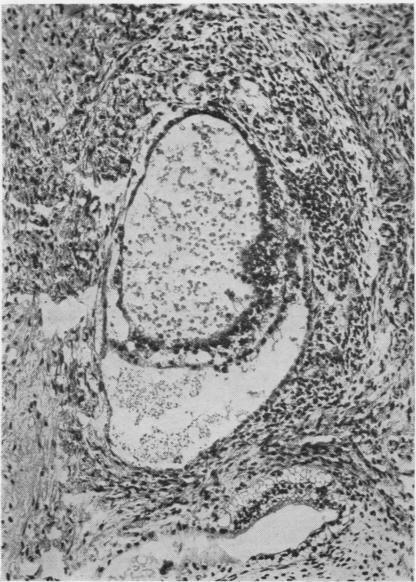

Developmental stages of embryo-like bodies in teratoma testis.